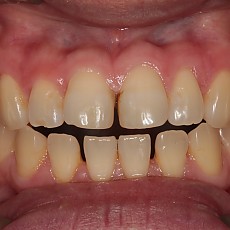

시술전후사진 6 페이지

Total 189건 6 페이지